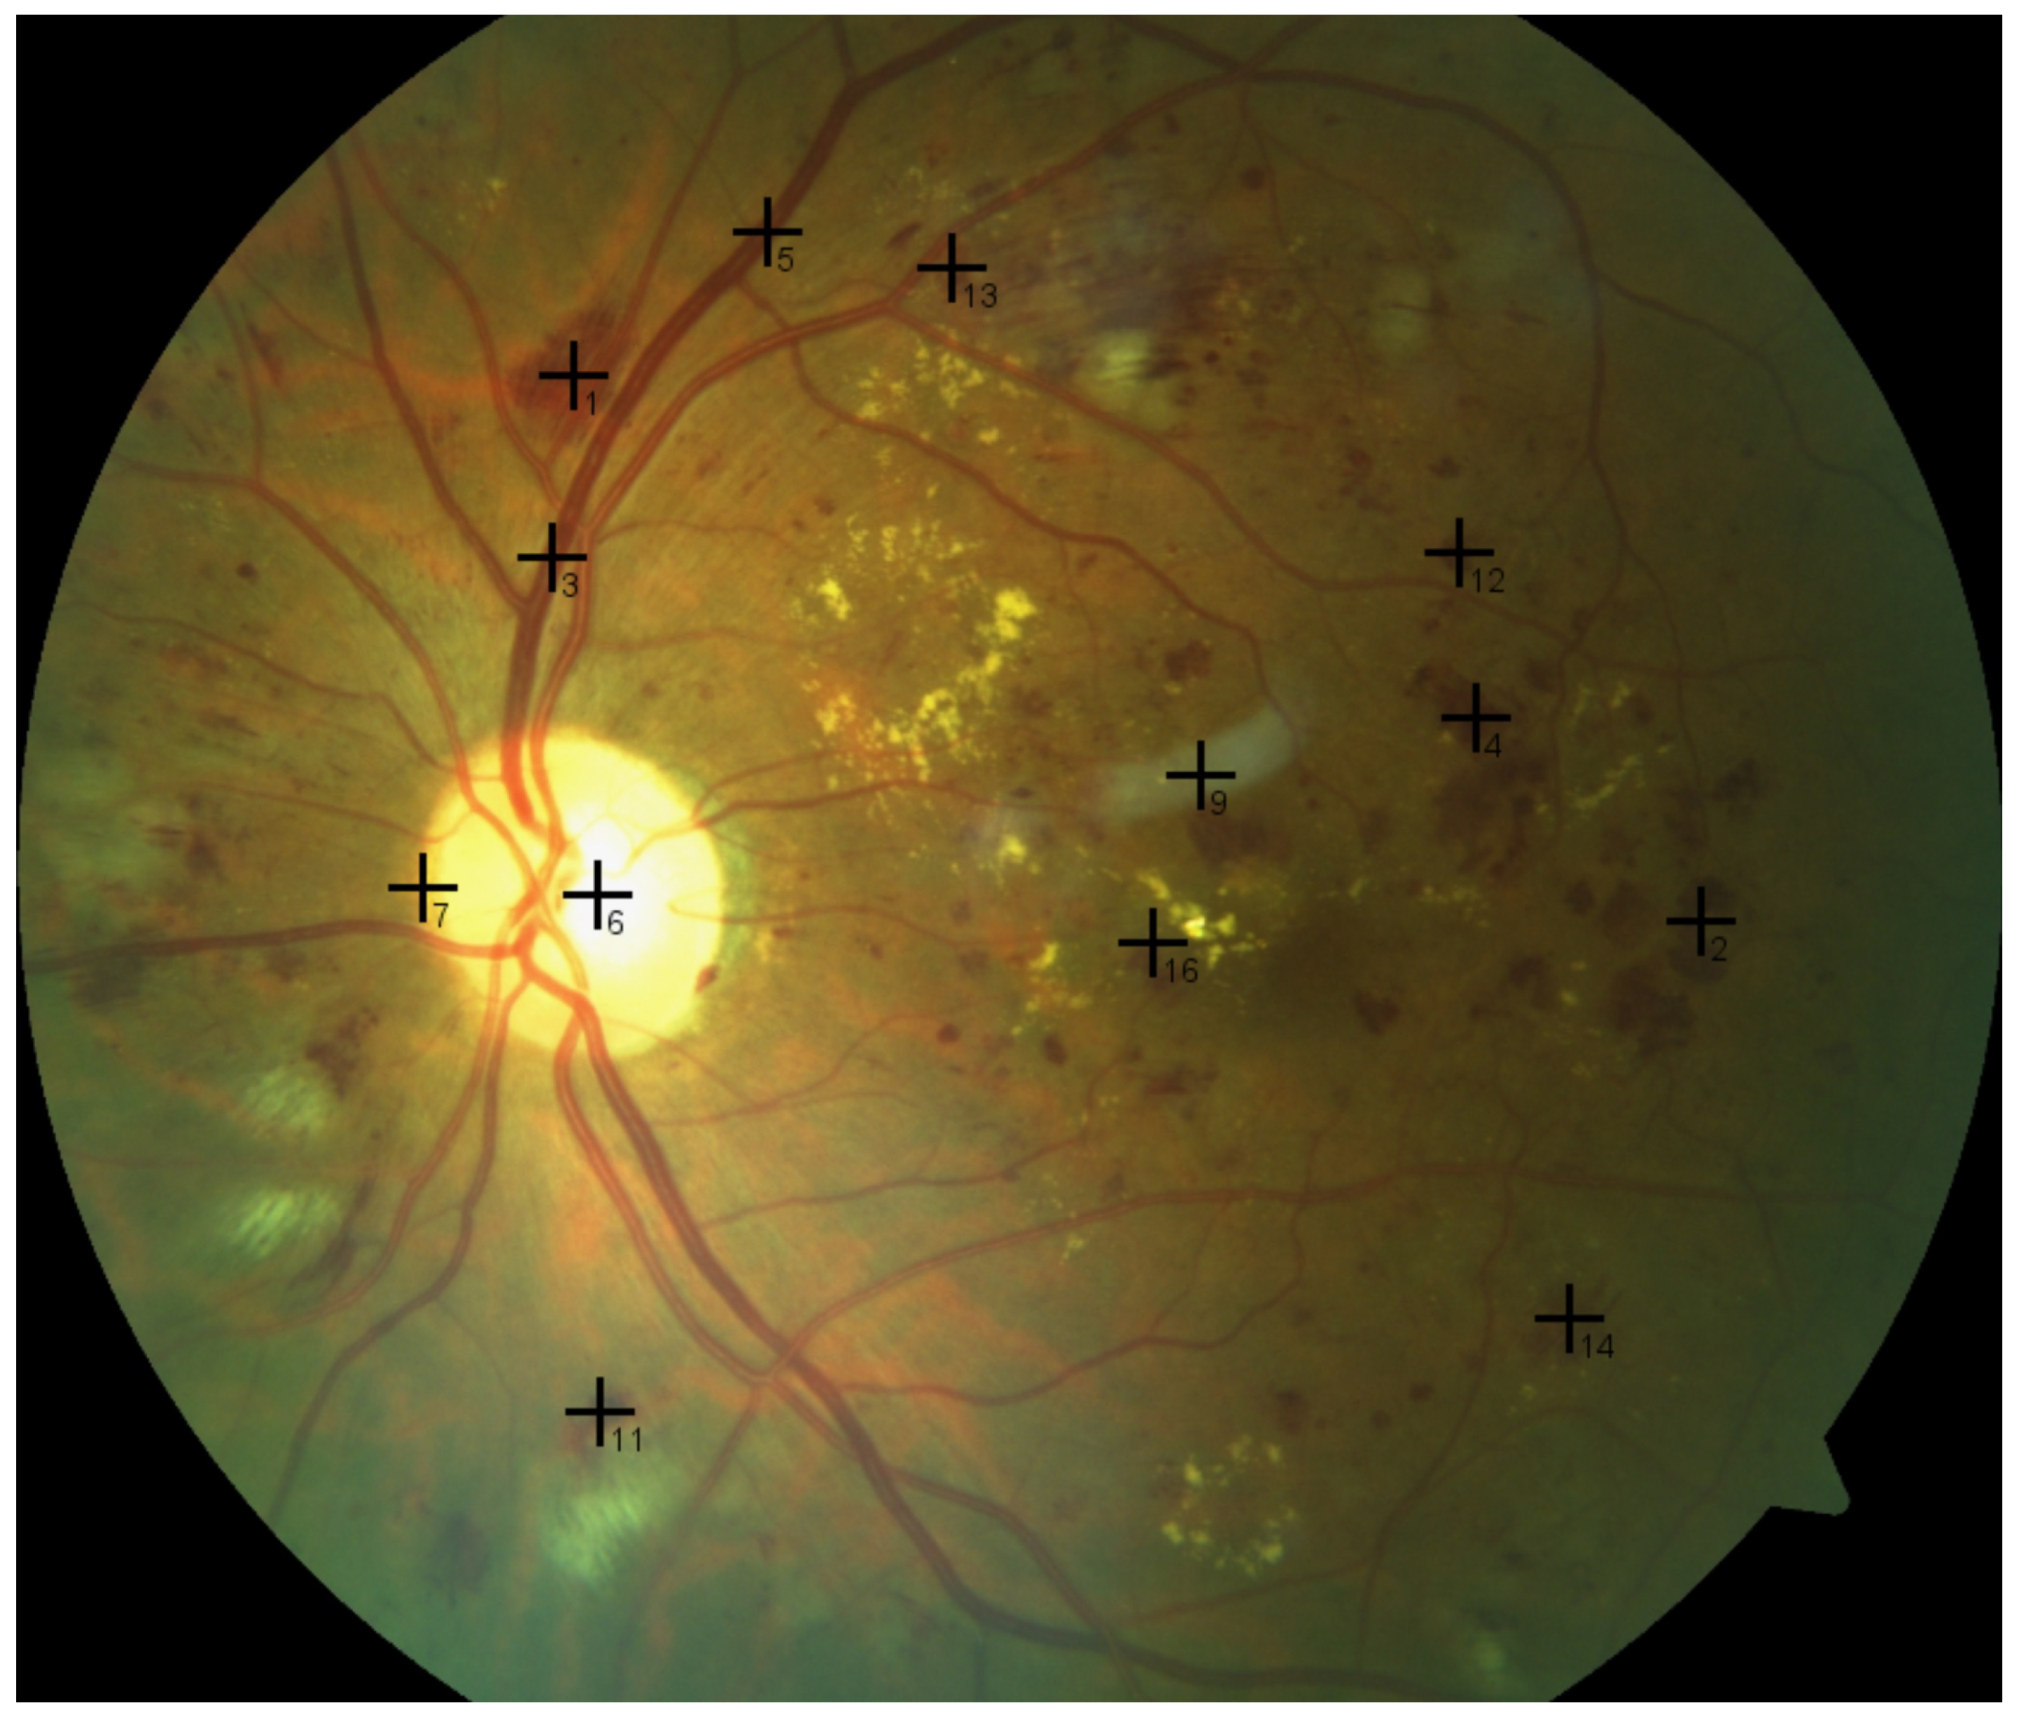

Luckily, images of the retina can help in diagnosing several retinal diseases, including DR and glaucoma [9]. This process is usually carried out and interpreted manually, which is laborious and prone to error due to minute image details, as shown in Figure 1. Consequently, if this process is automated, it would help ophthalmologists with a supportive tool that makes both diagnosis and decision making faster, easier, less expensive, and more accurate. To this end, computer vision and imaging techniques, such as those in the present work, can be leveraged.

Figure 1.

The subtle and tiny intensity variations in the fundus image are too difficult to identify by the naked eye, and this is where the proposed CAD system can help.

- Subtle and tiny variations between intensity values of retinal objects, as shown in Figure 1, can cause errors;

Despite the huge body of work in the field of eye CAD systems, there is a gap in handling and classifying more than one retinal disease at once (direction six above), in particular distinguishing between cases of DR, glaucoma, and normal conditions in fundus images. This could be due to the scarcity of publicly available fundus images, especially ones with both glaucoma and DR. It could also be due to the fine and subtle differences between the intensity values of different pathological patterns (pixels) in the images, as shown in Figure 1. The present work is intended to bridge this gap.